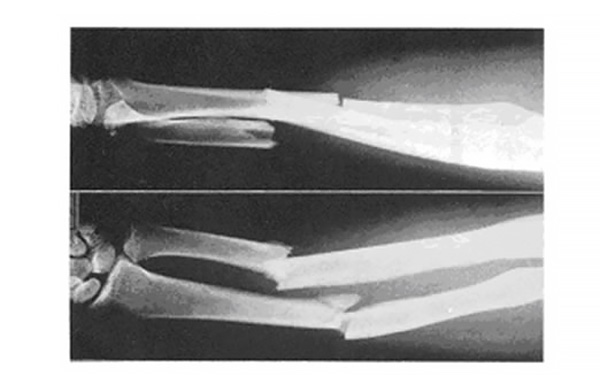

下の画像は、上段が前腕の横方向から、下段が前腕の正面からそれぞれ撮影したX線画像です。

橈骨と尺骨の中央部分が横に折れており、明らかに骨がずれて転位していることがわかります。